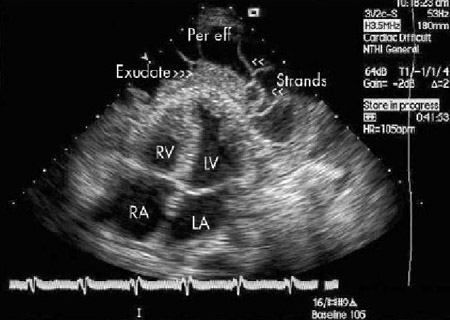

Assessment of pericardial effusion

Apical 4-chamber view of a 2-dimensional echocardiogram of a patient with tuberculous pericardial effusion; LA = left atrium, LV = left ventricle, Per eff = pericardial effusion; RA = right atrium, RV = right ventricle

From: George S, Salama AL, Uthaman B, et al. Heart. 2004; 90:1338-1339